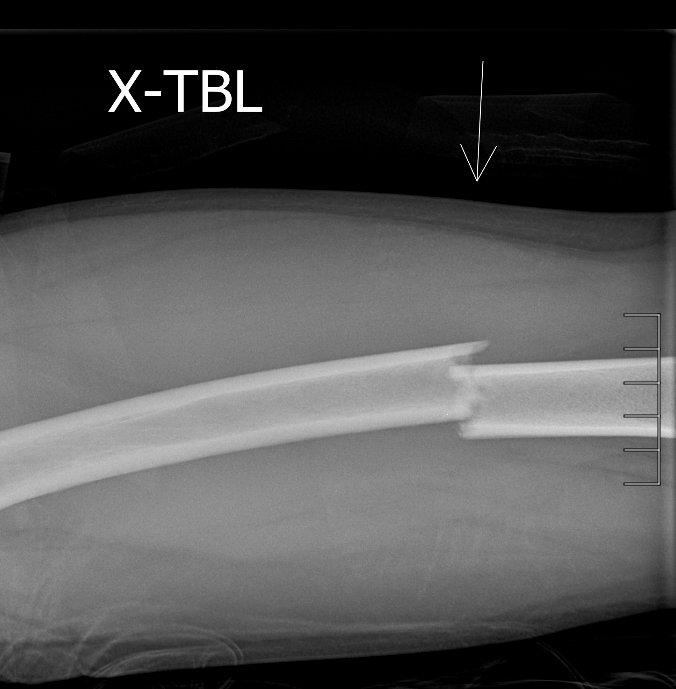

Info Images Findings Impression Reco/Acuity Case Images View Images / Launch Visage Case Notes History 2-month-old presents with decreased right arm movement, increased fussiness, and increased sleepiness for 2 days. Suspected non-accidental trauma. Exam Skeletal survey Prior Study none Dicom View Reference Material

Section 1 Submit Findings CB1550 Findings Skeletal Survey - Technique Check Skull AP/Lat Yes No Cervical and Thoracolumbar spine Yes No Chest X-Ray Yes No Ribs – Left/Right Oblique Yes No Abdominal X-Ray Yes No Pelvis with both hips Yes No Bilateral Humerus, Forearm, Hand Yes No Bilateral Femur, Tibia/fibula, feet Yes No Any additional lateral views of the extremities Yes No The exam is over or under penetrated. Yes No The exam may or may not be limited by overlying structures or soft tissues, body habitus, patient positioning, support devices, or motion. Yes No The area of concern is indicated by the patient, technologist, or care provider. Yes No The area of concern is included on the exam. Yes No Soft Tissues There is soft tissue swelling, indistinctness of fat/muscle planes, gas, or laceration in the area of clinical concern. Yes No There is an effusion, fat pad displacement, or fat fluid level. Yes No There is a radiodense or lucent foreign body. Yes No There are other densities, calcifications, post-surgical changes, or support devices in the soft tissues. Yes No Any support lines/tubes. Yes No Bone There is a break or interruption of the continuity of the cortical or cancellous bone. Yes No There is overriding of the trabeculae with apparent sclerosis. Yes No There is displacement of a fracture fragment. Yes No There is bowing of the bone in addition to the fracture at the apex of the bowed bone concerning for the greenstick. Yes No There is a spiral fracture of the leg concerning for toddler’s fracture. Yes No There is abnormal angulation or bulging of the cortical surface relative to the normal cortex which could be from a buckle or torus fracture. Yes No There is a displaced fragment which may be from avulsion by a tendon, ligament, or joint capsule or from a comminuted or other fracture. Yes No The stress trabeculae or other trabeculae of the cancellous bone are interrupted or otherwise abnormal. Yes No There is subperiosteal or endosteal reaction which could indicate a healing or subacute fracture or other abnormality. Yes No There is hard/soft callus formation. Yes No There is remodeling of the bone. Yes No There is a corner fracture or metaphyseal lesion that could be from nonaccidental trauma. Yes No There are multiple fractures of different ages. Yes No There are vertebral body/spinous process fractures. Yes No There are rib fractures. Location - posterior or lateral. Yes No There is scapular/sternal fracture. Yes No There are fractures of the digits. Yes No There are wormian bones. Yes No There are intrasutural bones. Yes No There is metaphyseal abnormality (lucencies, increased density, erosion) which may be from something other than injury such as stress, metabolic disease (e.g. rickets with loss or distortion of the zone of the provisional calcification), neoplasm (e.g. leukemia), heavy metals, inflammation, or infection. Yes No There are metaphyseal spurs. Yes No There are bony deformities involving multiple bones. Yes No The bones are gracile. Yes No There are non-healing fractures. Yes No There is/are focal or multifocal lytic/lucent, blastic/sclerotic or mixed density lesion(s) or other abnormality. Yes No Overall bone density is increased or decreased with or without thinning or thickening of the cortical or cancellous bone. Yes No Growth plates, ossification centers, apophyses The growth plate(s) is/are abnormal. Yes No There is widening of the physis from a fracture with or without displacement of the epiphysis (Salter-Harris I). Yes No There is a fracture through the physis which then extends into the metaphysis with or without angulation or displacement (S-H II). Yes No There is a fracture through the physis which then extends into the epiphysis and is intra-articular, with or without angulation or displacement (S-H III). Yes No There is a fracture through the metaphysis, physis, and epiphysis which extends into the joint space with or without angulation or displacement (S-H IV). Yes No There is narrowing of the physis from a compression fracture (S-H V). Yes No The apophysis, epicondyle, secondary ossification center, or accessory ossicle is displaced or otherwise abnormal. Yes No The ossification centers are underdeveloped. Yes No Joints and alignment There is an effusion, fat pad displacement, or fat fluid level. Yes No The epiphysis or subchondral bone is fractured, interrupted, flattened, compressed, impacted, displaced, or otherwise abnormal. Yes No There is an intra-articular loose body or chondrocalcinosis. Yes No The joint is widened, narrowed, dislocated, malaligned, or incongruent. Yes No There is pseudoarthrosis. Yes No Other findings There are developmental changes or other anatomic variants or other existing conditions that may or may not be contributing to symptoms which can or should be further evaluated non-emergently or are otherwise incidental. Yes No The remainder of the exam is abnormal for age. Yes No The lungs show focal airspace opacity. Yes No There is pneumothorax. Yes No There is organomegaly. Yes No There is intra-abdominal calcification. Yes No There is displacement of the bowel loops. Yes No There is free intraperitoneal air. Yes No The bowel loops are dilated/obstructed. Yes No There is paraspinal soft tissue abnormality. Yes No